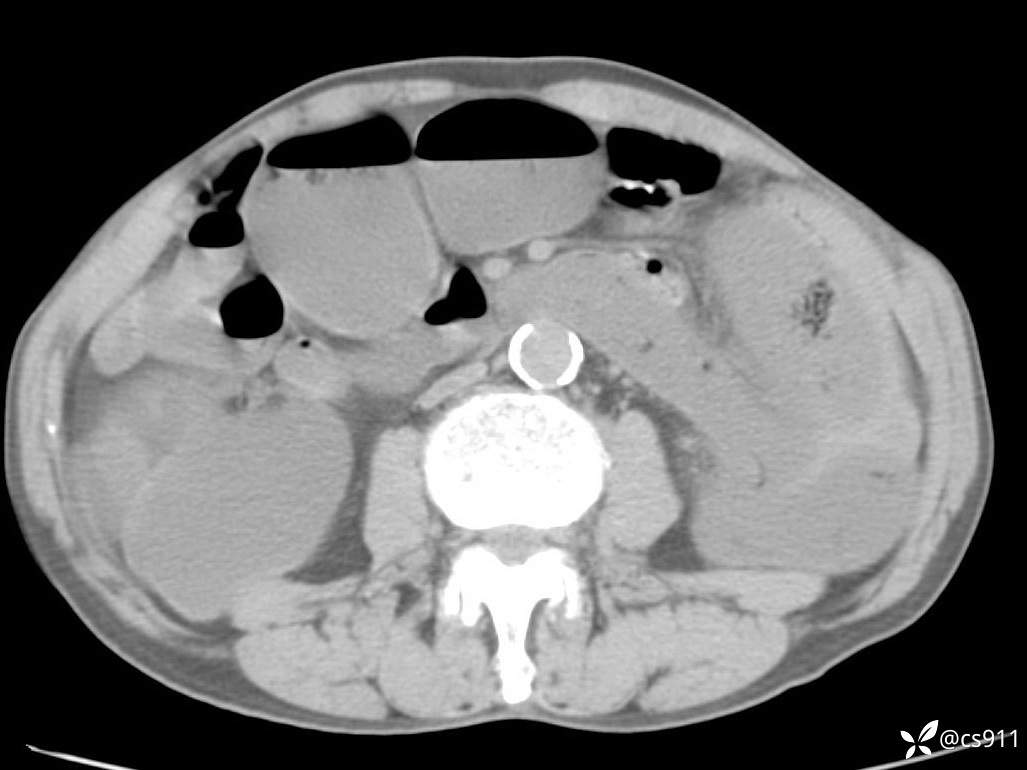

急腹症之急诊CT,原因?答案公布

男,77岁,腹痛、腹胀伴恶心呕吐1天。呕吐胃内容物,非喷射性呕吐,有咖啡色样胃内容物,诉有胃穿孔病史。查体:全腹平,下腹部压痛,全腹无反跳痛,叩诊呈浊音,移动性浊音阴性,肠鸣音减弱,1-2次/分。肛检:直肠未扪及明显肿物,可触及大量粪块。

T 36.6℃ P 80次/分 R 26次/分 BP 100/60mmHg

白细胞(WBC) H 14.55 10e9/L 4-10

中性粒细胞百分率(NEUT%) H 85.7 % 40-75

血淀粉酶(AMY) HH 1859 U/L 35-135

癌胚抗原(CEA) H 27.44 ng/ml 0-5

呕吐物 潜血试验 * 阳性 阴性

患者轮椅入室检查神志清楚, 能配合摆位和呼吸